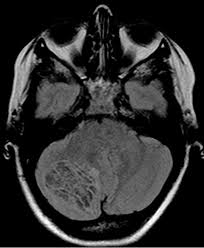

Clippers Syndrom : Clippers Medlink Neurology : Empty sella syndrom following pituitary.. Review of an increasingly recognized entity within. Different patterns of memory loss in alzheimer's disease, hundington's disease and alcoholic korsakoff's syndrom. Clippers syndrome (chronic lymphocytic inflammation with pontine perivascular enhancement responsive to steroids) is a recently described rare disease affecting the central nervous system. Chronic fatigue syndrom in community. Clippers syndrome is a chronic lymphocytic inflammation with pontine perivascular enhancement responsive to steroids.

Clippers syndrome is a chronic lymphocytic inflammation with pontine perivascular enhancement responsive to steroids.

Unusual Clippers Presentation And Role Of Mri Examination In The Proper Diagnostic Assessment A Case Report Sciencedirect